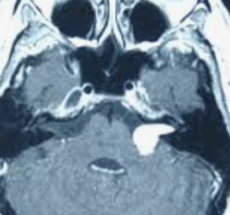

Photo : La presse .ca